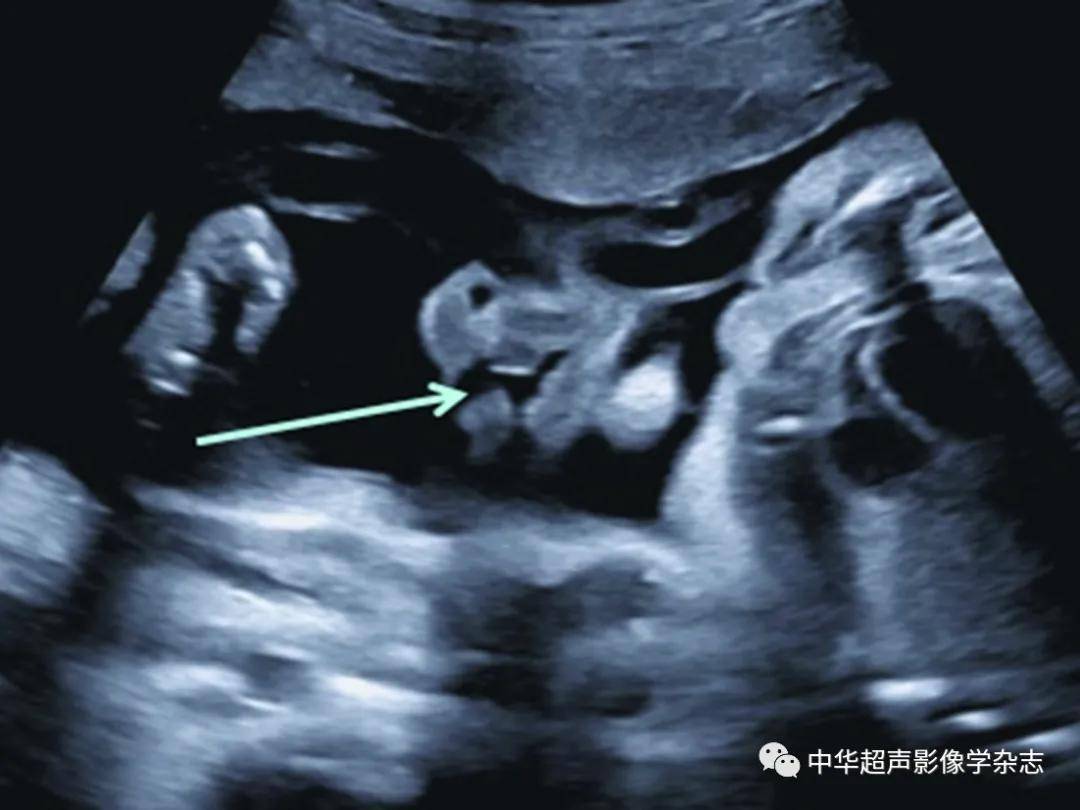

唇裂b超图侧面图

在妊娠20~24周超声检查时,应通过观察鼻唇冠状面判断上唇是否有唇裂

(箭头所示);b:正常胎儿面部正中矢状面下唇裂非常罕见且超声诊断困难